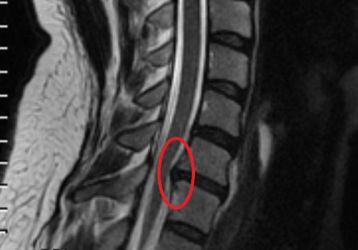

Симптомы и методы лечения секвестрированной грыжи позвоночника

Как вылечить секвестрированную грыжу позвоночника: причины, виды патологии, симптомы и диагностика. Медикаментозное лечение, операция и реабилитация.